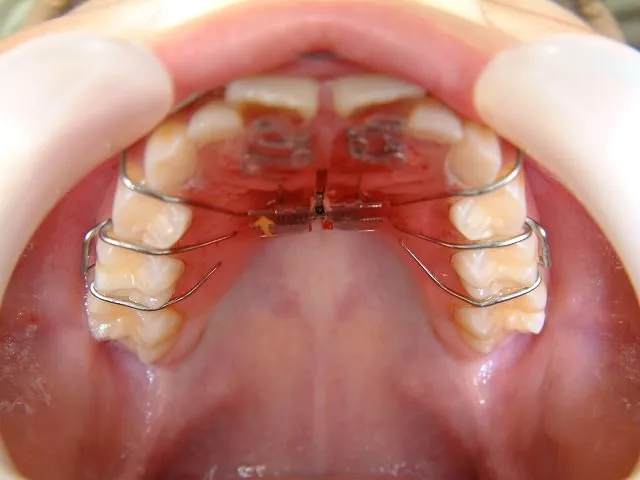

急速拡大装置

上顎の歯列の幅を急速に広げる際に使用される装置です。装置の中央にある拡大ネジを調整することで、歯列を押し広げます。通常の矯正装置と比べて、短い期間で治療を終えることが可能です。